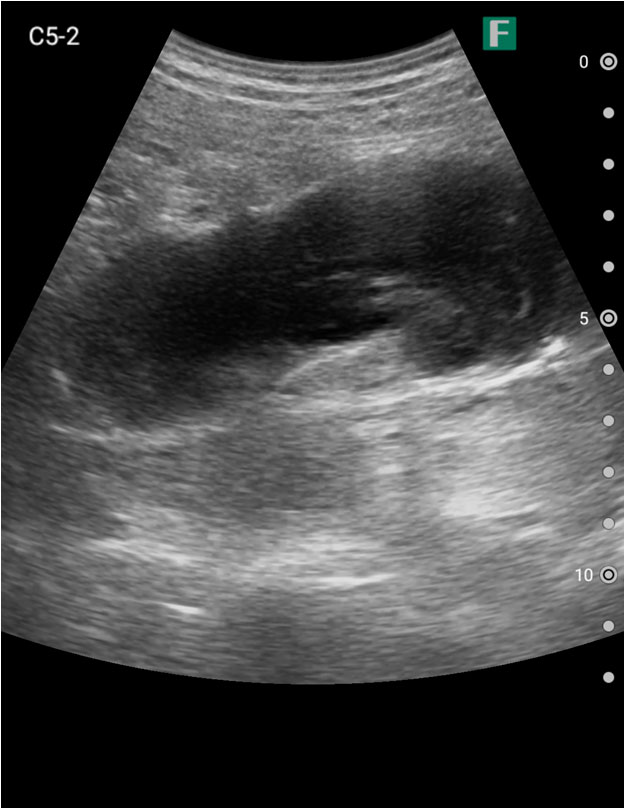

もう一つは入院患者様に対しての具体的な使用事例を紹介します。朝の回診の際にiViz airを使用し、例えば腹水のある患者様を診た際は、「今日は水の量が少なく、そこまでお腹は張ってないですね」、「今日はここに水が溜まっているんですけど、昨日より少ないですよ」など、日々の状態を患者様ご本人に伝えるようにしています。スマホで実際の画像も簡単にお見せできるので、患者様に実際に見ていただくことで少しでも不安を和らげてもらえるように心がけています。

そうして積極的に話をすると、不安そうな表情をする患者様はあまりいらっしゃらない印象を受けています。iViz airがあると患者様と会話をするきっかけにもなるため、コミュニケーションツールとしても実用的だと感じた事例でした。